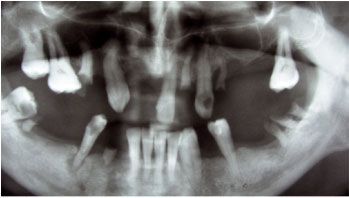

Вот такую картину состояния зубочелюстной системы мы увидели на рентгеновском снимке (ортопантомограмме): обнажение корневой части зубов от 30 до 60 процентов, уменьшение объема кости, как на верхней так и на нижней челюстях.